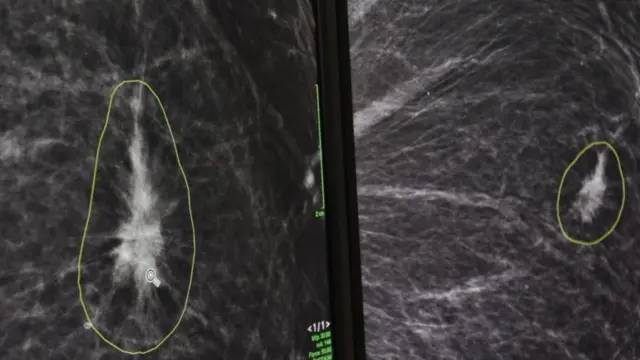

او به برنامه کلیک بیبیسی نشان داد که چگونه این نرم افزار با استفاده از نتایج ماموگرافی ناشناس عمل میکند.

او گفت: «آنچه اکنون میبینیم خانمی است که پستان چپ و راستش تحت ماموگرافی قرار گرفته است، در این تصاویر به دنبال تفاوتها میان دو پستان هستیم.»

با کلیک بر روی یک دکمه، رادیولوژیستها می توانند تفاوتهای شناسایی شده توسط هوش مصنوعی بین دو اسکن را مشاهده و بررسی کنند.

دکتر لیپ با اشاره به ناحیهای از تصویر که توسط نرم افزار هوش مصنوعی حلقه شده، آن را نقطه اصلی نگرانی خواند.